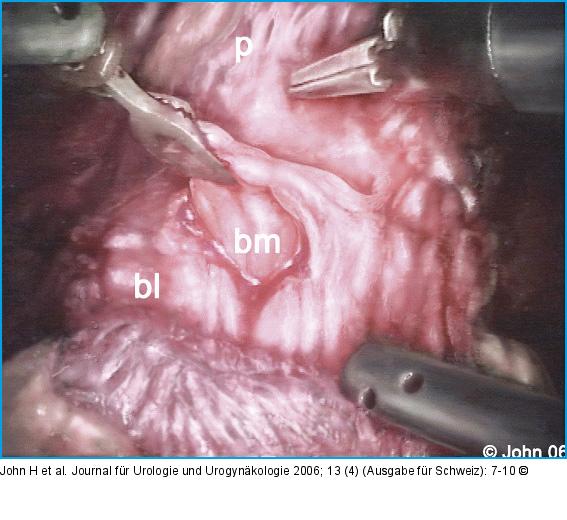

Abbildung 4a-i: DaVinci-Prostatektomie - Technik Die endopelvine Faszie wird beidseits inzidiert (a) und der Plexus Santorini aus Hämostasegründen durchstochen (b). Der Blasenhals wird schonend abgesetzt (c), die Adnexe abgesetzt (d) und die Prostata nach Eröffnen der Denovillierschen Faszie (e) vom Rektum abgeschoben. Die neurovaskulären Bündel werden nach Möglichkeit geschont (f). Apikal wird ein möglichst langer Harnröhrenstumpf gebildet (g) und das Präparat abgesetzt. Nach der vesiko-urethralen Anastomose (h) kann die Prostata über einen Endobag durch den infraumbilikalen Zugang geborgen werden (i). |

Die endopelvine Faszie wird beidseits inzidiert (a) und der Plexus Santorini aus Hämostasegründen durchstochen (b). Der Blasenhals wird schonend abgesetzt (c), die Adnexe abgesetzt (d) und die Prostata nach Eröffnen der Denovillierschen Faszie (e) vom Rektum abgeschoben. Die neurovaskulären Bündel werden nach Möglichkeit geschont (f). Apikal wird ein möglichst langer Harnröhrenstumpf gebildet (g) und das Präparat abgesetzt. Nach der vesiko-urethralen Anastomose (h) kann die Prostata über einen Endobag durch den infraumbilikalen Zugang geborgen werden (i). |